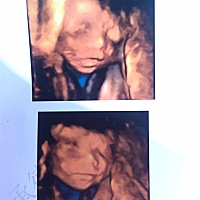

这是有了吗?